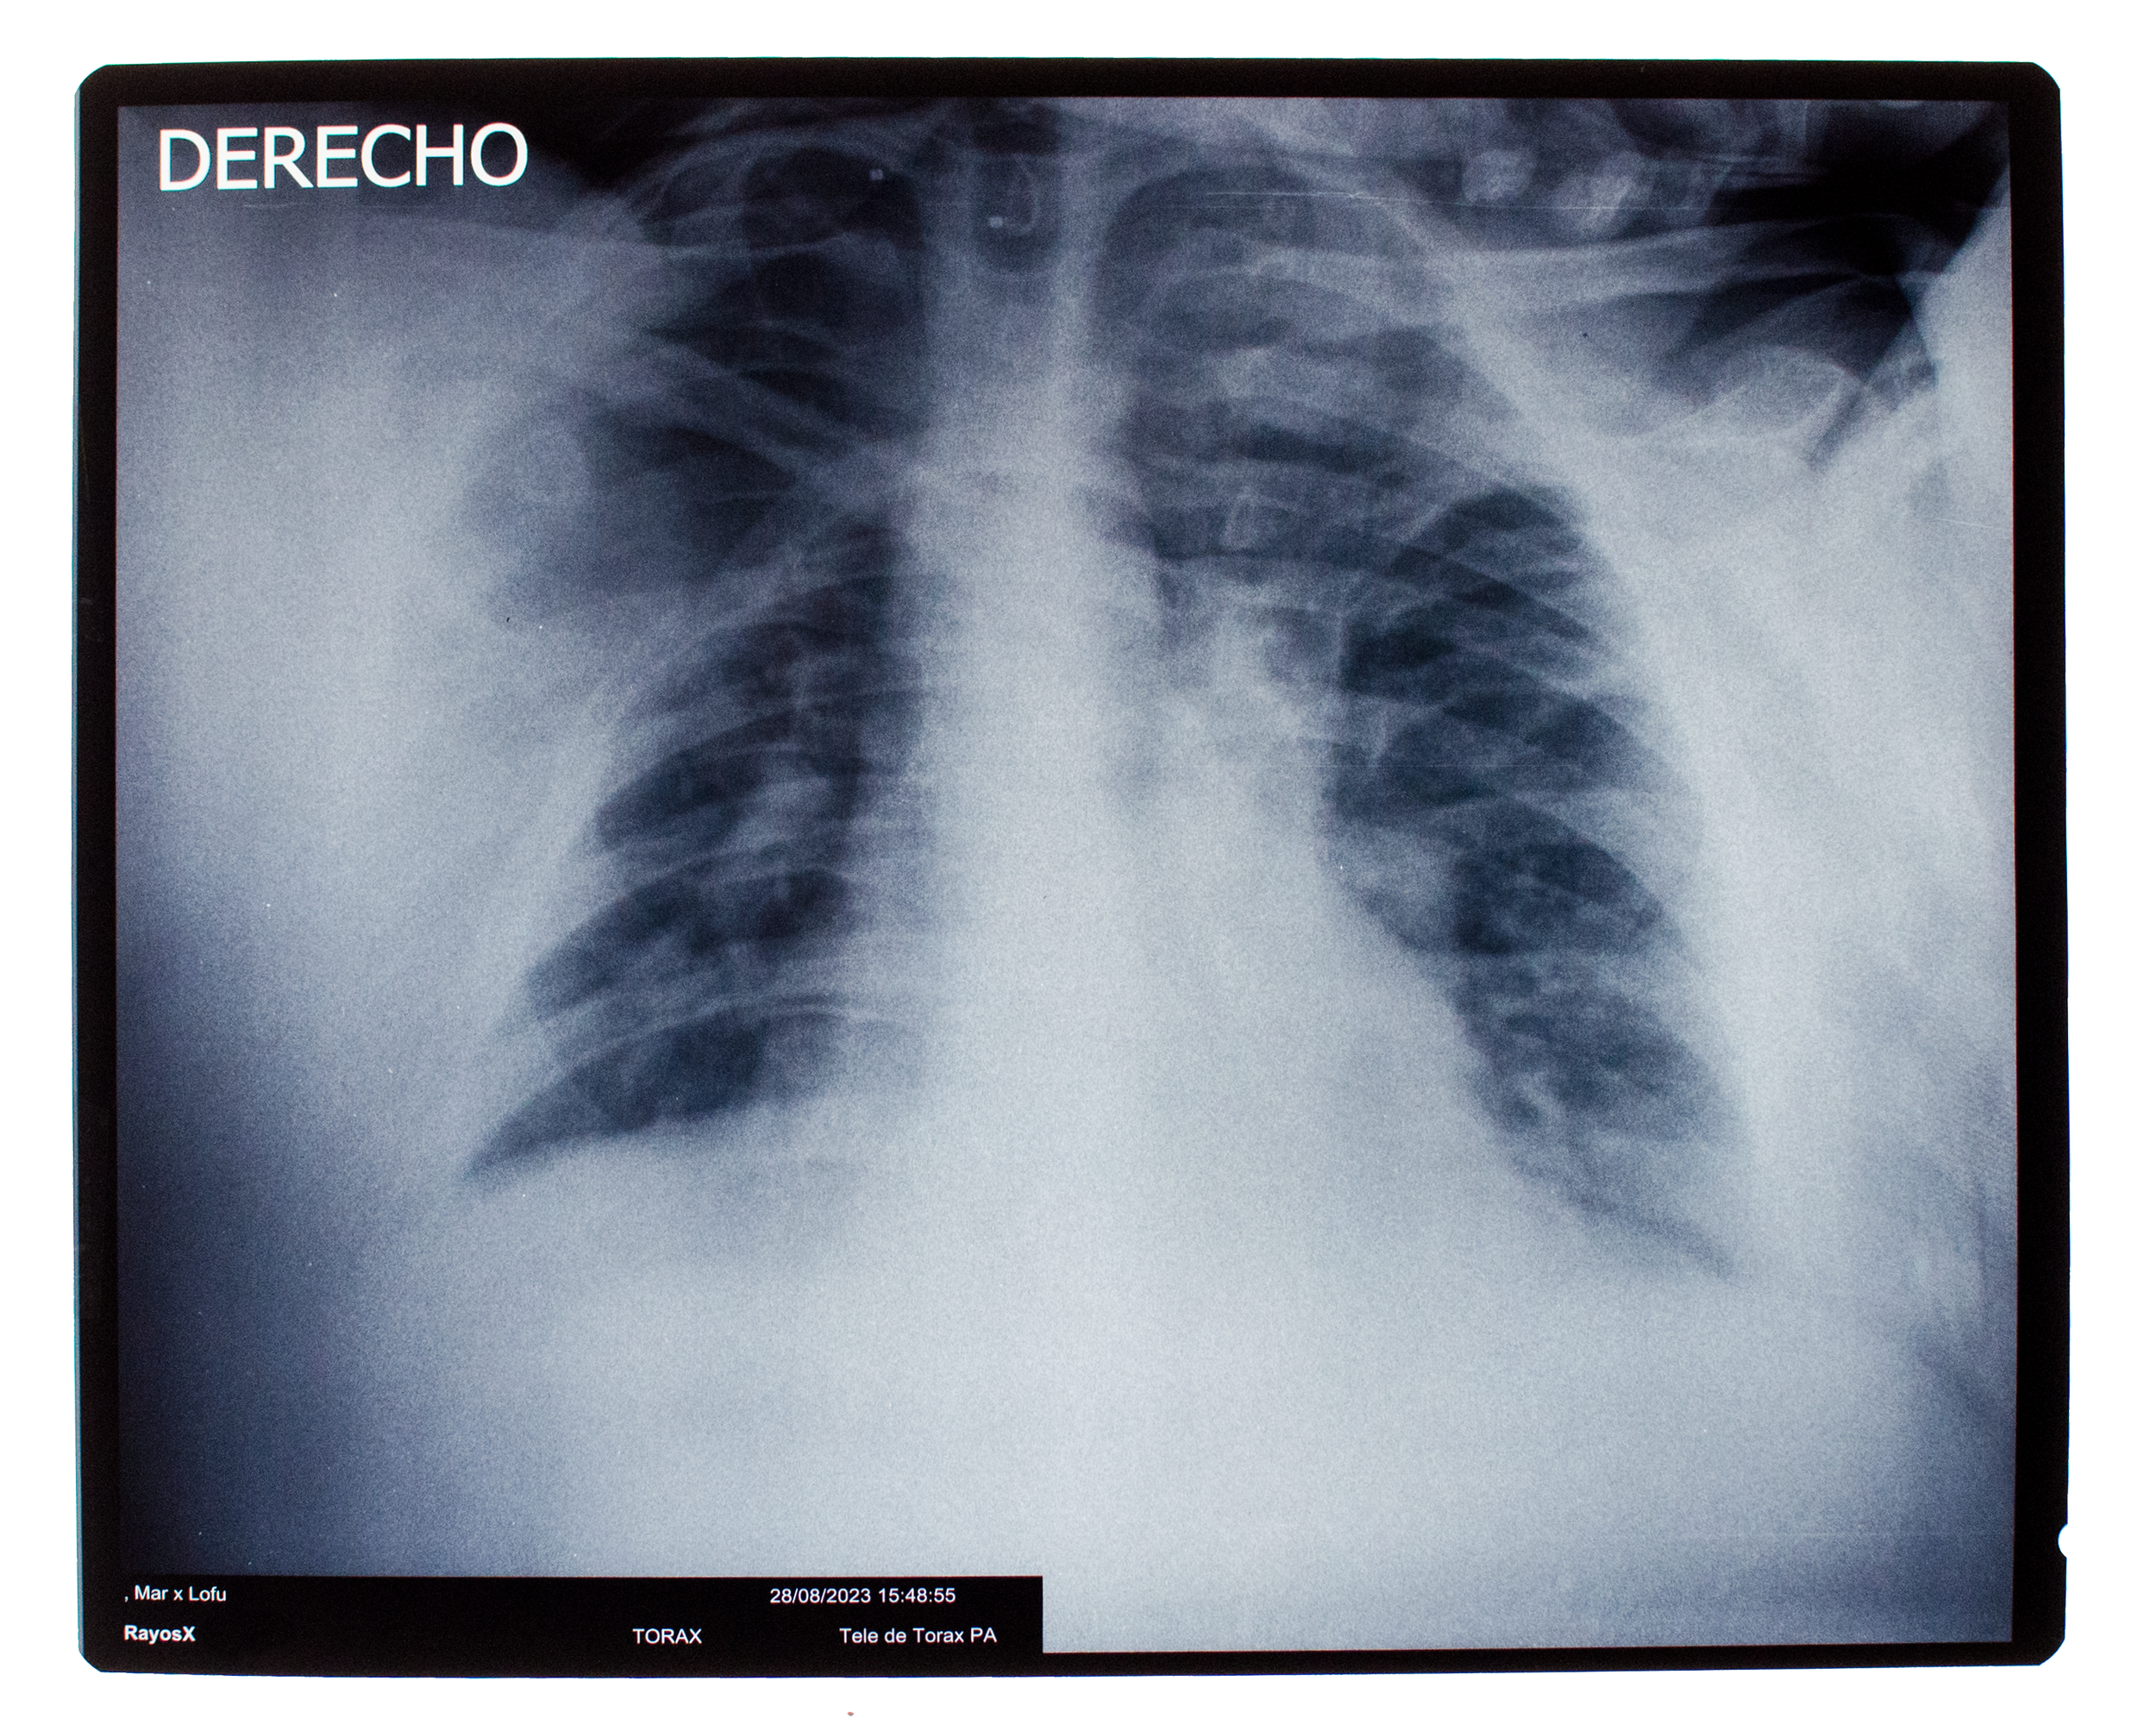

De un intento por definir la esencia básica de una acción fisiológica y proxémica se derivan tres piezas que abordan diferentes elementos de un abrazo: una visión interna a través de la radiografía, el retrato en cianotipia directo de un negativo de 35mm y un micro-relato del suceso.

Radiografía, cianotipia, texto. 2023